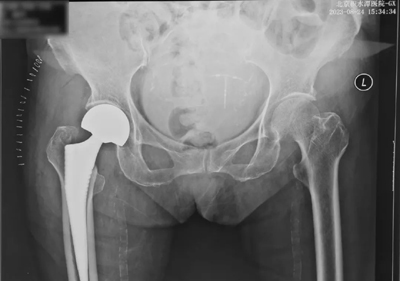

8月14日,67岁的梁阿姨在买菜途中不小心摔倒,右髋疼痛,无法站立,被家人紧急送到附近医院,拍片显示右侧股骨粗隆间骨折,当地医生告知这是老年骨质疏松骨折,需要手术。听说北京积水潭医院有老年髋部骨折的绿色通道,梁阿姨当即就被转诊到北京积水潭医院新街口院区创伤骨科急诊。经过急诊快速通道,完成术前检查和麻醉评估,准备手术,但术前检查显示梁阿姨血压、血糖较高,同时存在肾功能不全、低氧血症情况。这可把梁阿姨一家急坏了。主管医师立即请心内科、内分泌科、肾内科及呼吸内科会诊。在专家团队的精心治疗下,梁阿姨的各项指标均达到手术标准,于7天后完成了人工股骨头置换术手术。术后第一天,梁阿姨能够坐立在床边,第二天梁阿姨能够借助助行器短距离步行,第三天梁阿姨出院。